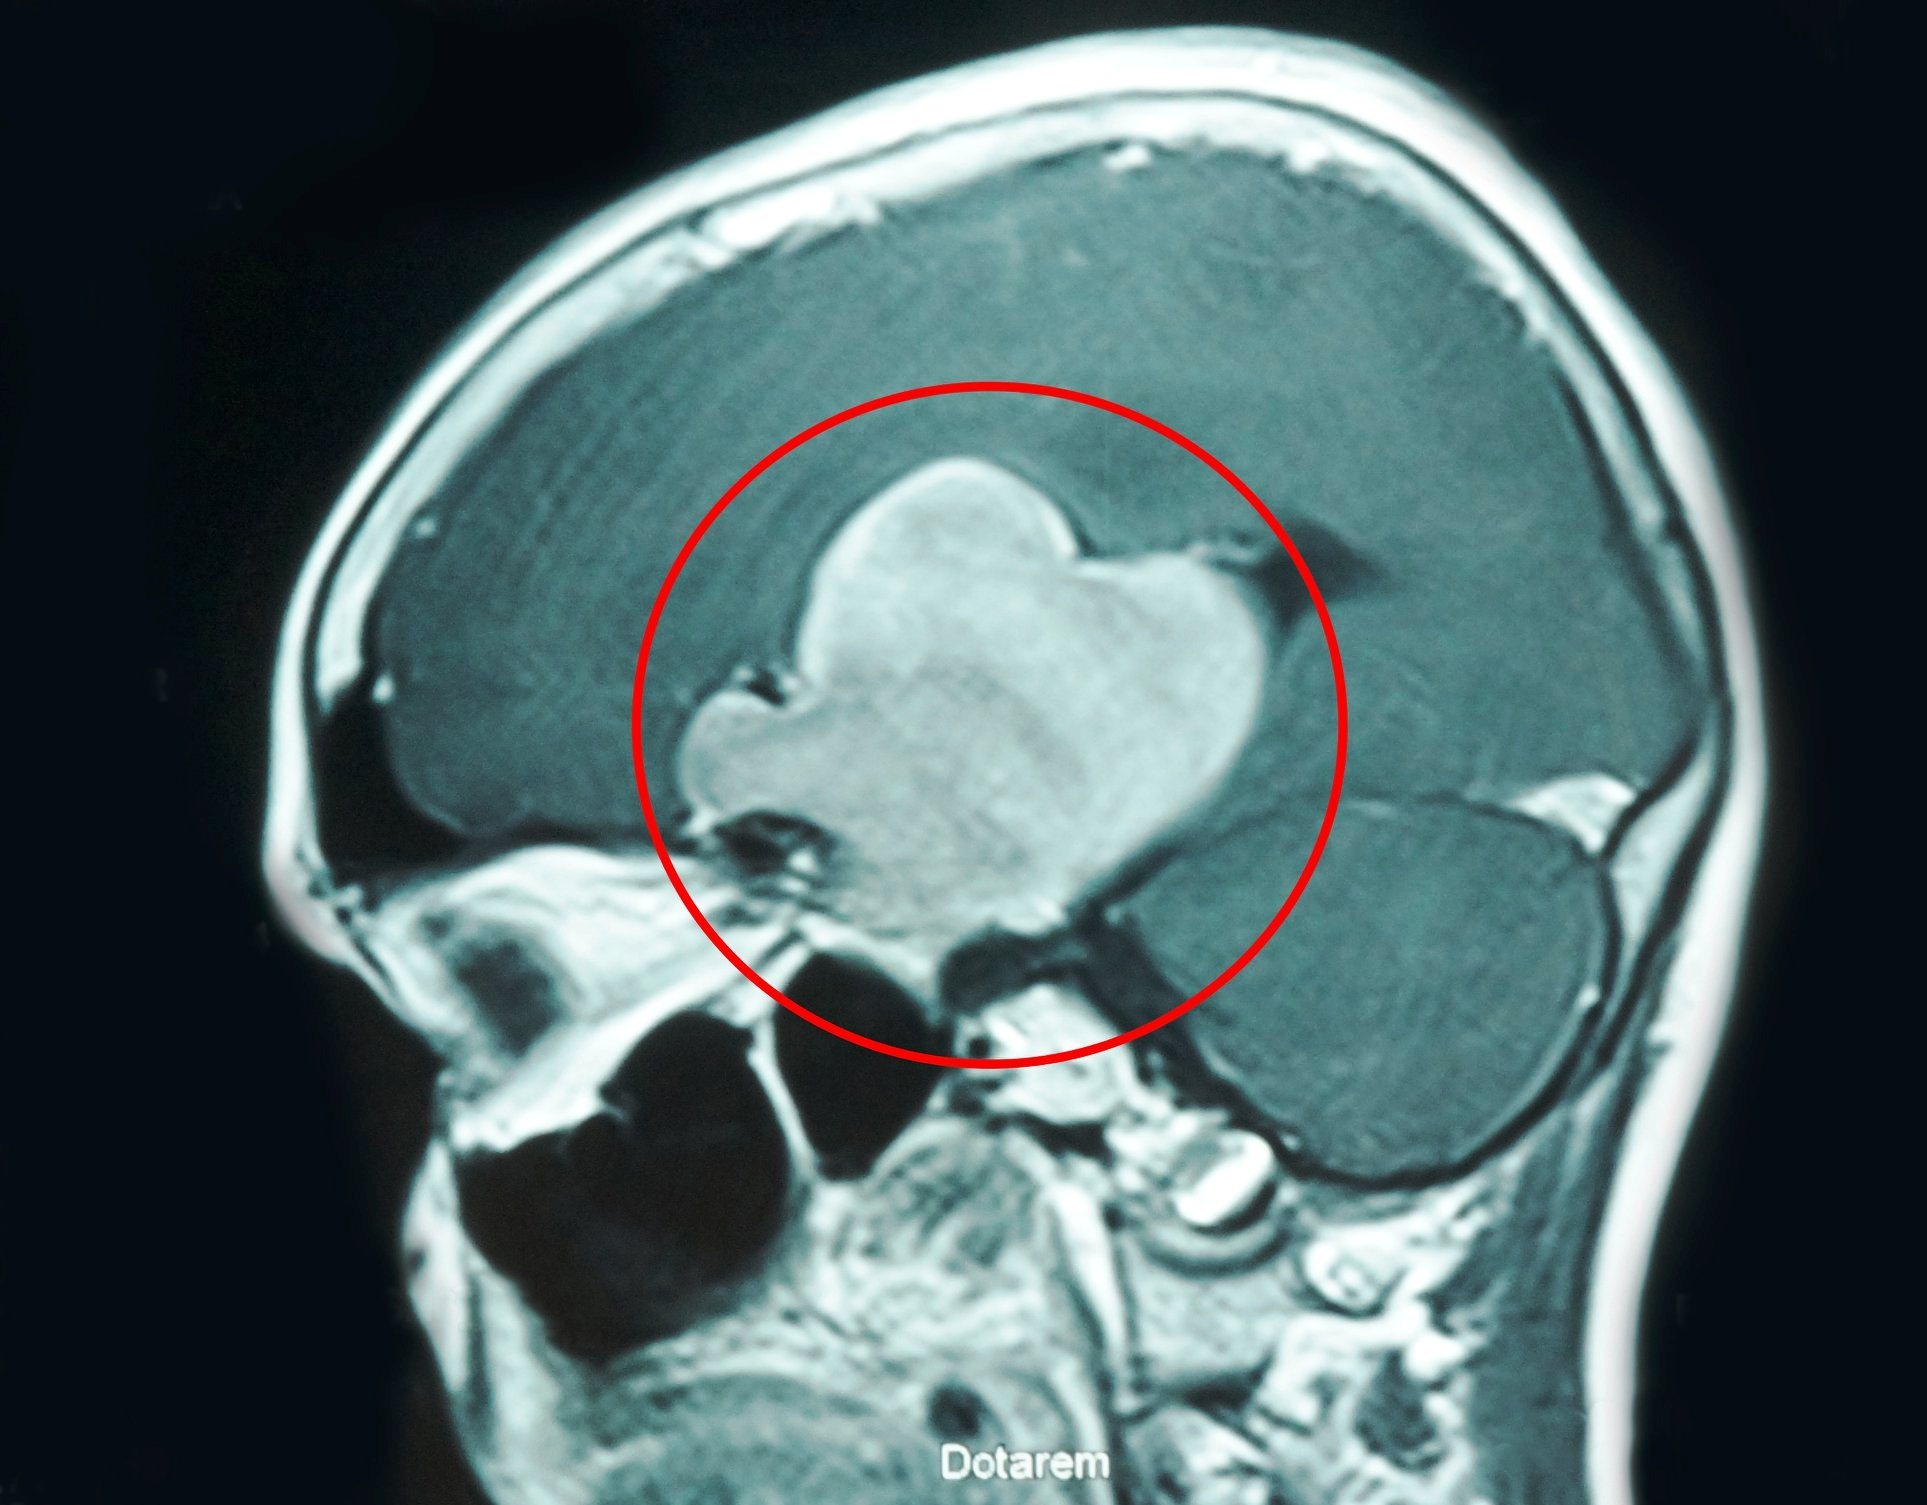

Bệnh viện Đa khoa Xuyên Á (Củ Chi, TP.HCM) đã tiếp nhận một bệnh nhân nam (61 tuổi, ngụ Tây Ninh) nhập viện trong tình trạng đau đầu dữ dội, yếu liệt nửa người trái, tri giác lơ mơ, sức khỏe suy kiệt. Qua chẩn đoán hình ảnh, bác sĩ phát hiện ở bán cầu não bên phải bệnh nhân có một khối u lớn.

| Khối u não khiến bệnh nhân liệt nửa người đã được bác sĩ mổ tách thành công. Ảnh: Bệnh viện cung cấp |

Sau khi phát hiện khối u, bác sĩ tư vấn người nhà cần sớm phẫu thuật điều trị, vì khối u lớn sẽ chèn ép, gây nhiều tổn thương nghiêm trọng đến nhiều chức năng của cơ thể bệnh nhân như vận động, thị giác, nhận thức, thậm chí có thể tử vong.

Ê-kíp các bác sĩ chuyên khoa Ngoại Thần Kinh đã tiến hành phẫu thuật trong 5 tiếng để giải phóng, bóc tách và lấy trọn u ra khỏi não.